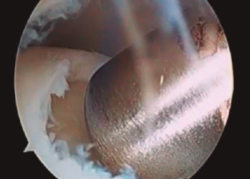

Figura 7. Intercambio de portales y comprobación de la correcta extracción en la zona donante.

- Artroscopia de rodilla empleando los portales convencionales anterolateral y anteromedial. Podemos obtener el cilindro bien de la vertiente femoral lateral o de la escotadura intercondílea. Somos partidarios de esta segunda localización por reconstruir mejor la convexidad del astrágalo.

- El instrumental extractor de la zona donante está sobredimensionado 1 mm para asegurar una correcta impactación y la estabilidad del implante (Figura 7).